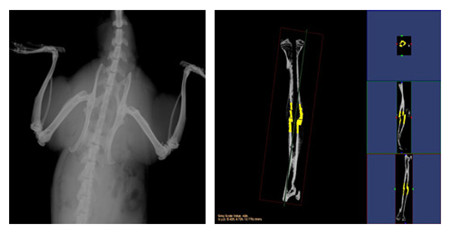

小動物CT服務通過采用錐形X線束,不僅能夠獲得真正各向同性的容積圖像,提高空間分辨率,提高射線利用率,而且在采集相同3D圖像時速度遠遠快于扇形束CT。可以對不脫鈣骨骼和動物牙齒進行microCT檢測服務,分析其內部結構和提供給您高清晰、高質量的掃描圖像。活體研究對象通常為小鼠、大鼠或兔等活體小動物,可以實現生理代謝功能的縱向研究,顯著減少動物試驗所需的動物數量;離體研究對象通常為離體標本(例如骨骼、牙齒)或各種材質的樣品,可分析其內部結構和力學特性。

操作簡單、影像系統性能強大,確保真正的容積透視和精確定量;集成的系統結構設計使從動物放置到數據分析與保存這一整套工作流程更高效。

結果示意圖:

小動物CT結果示意圖